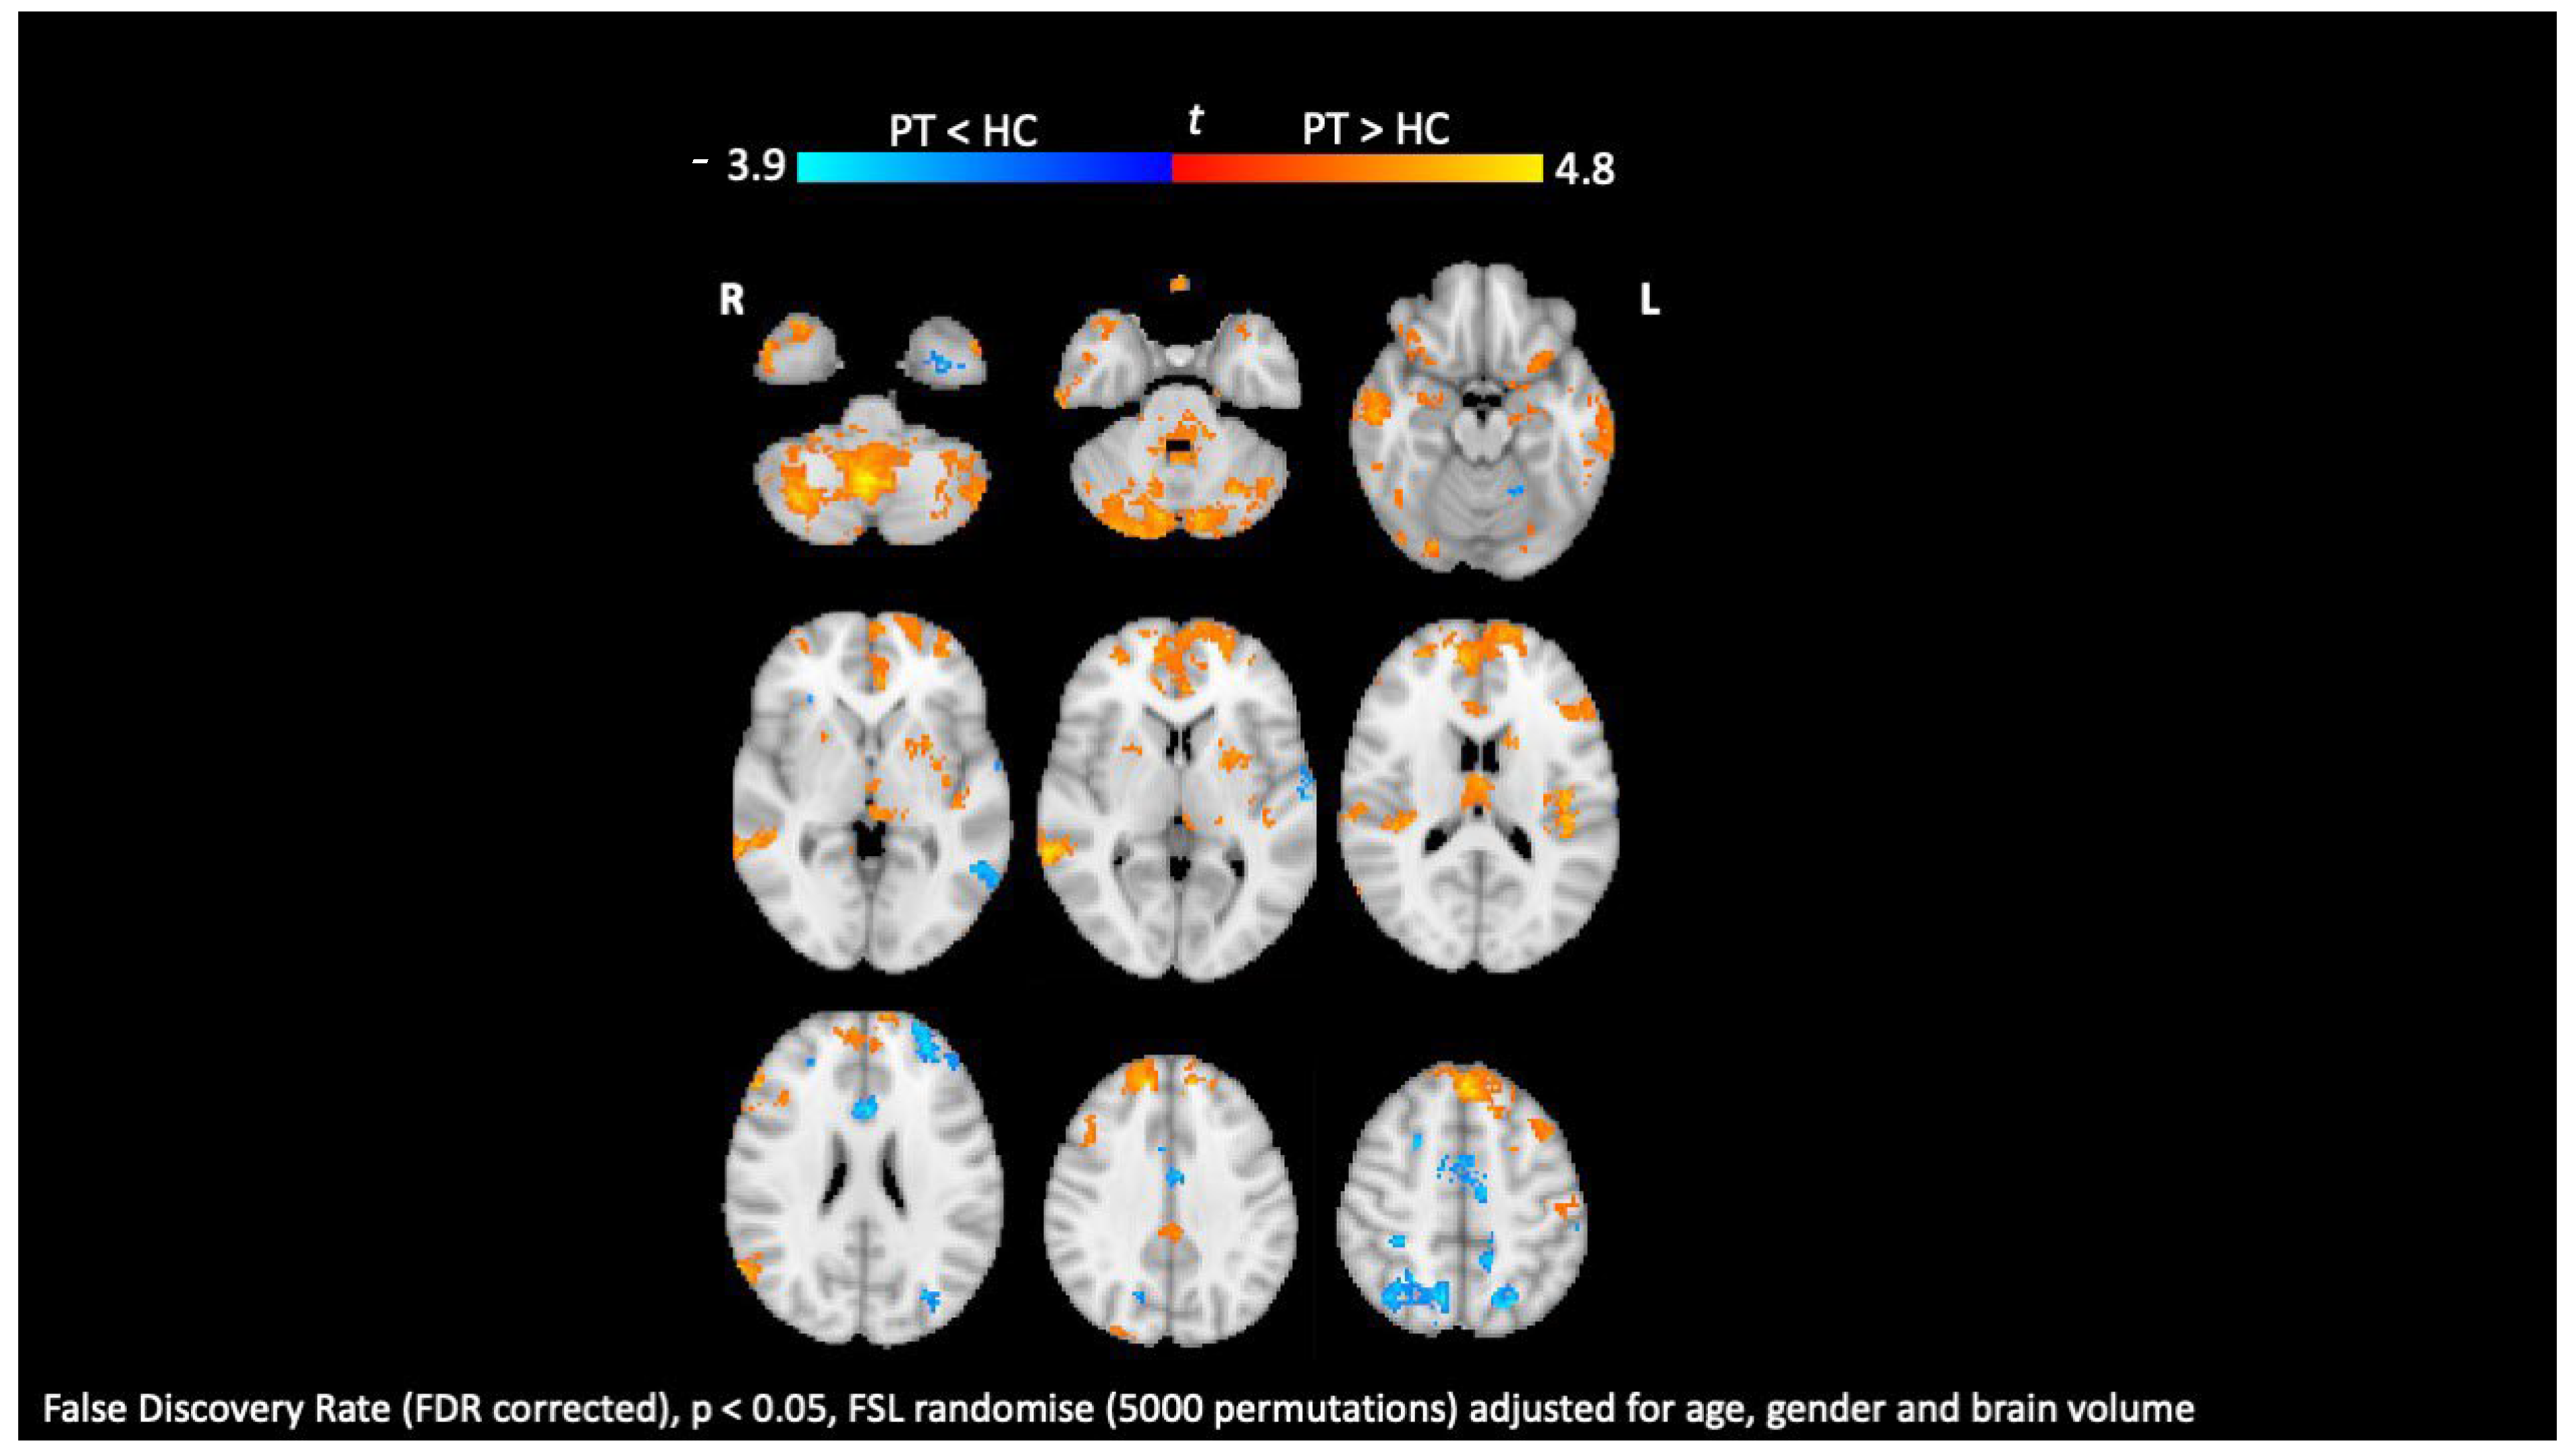

8. Diffusion Tensor Imaging

- Kolasa, M.; Hakulinen, U.; Brander, A.; Hagman, S.; Dastidar, P.; Elovaara, I.; Sumelahti, M. Diffusion tensor imaging and disability progression in multiple sclerosis: A 4-year follow-up study. Brain Behav. 2019, 9, e01194. [Google Scholar] [CrossRef] [PubMed]

- Lopez-Soley, E.; Martinez-Heras, E.; Solana, E.; Solanes, A.; Radua, J.; Vivo, F.; Prados, F.; Sepulveda, M.; Cabrera-Maqueda, J.M.; Fonseca, E.; et al. Diffusion tensor imaging metrics associated with future disability in multiple sclerosis. Sci. Rep. 2023, 13, 3565. [Google Scholar] [CrossRef] [PubMed]